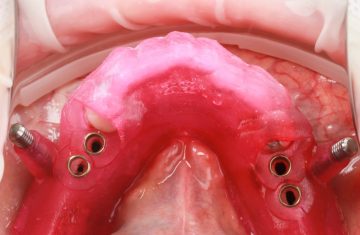

A Cirurgia Guiada é uma técnica inovadora, cujo implante dentário é feito sem cortes e pontos, portanto gerando maior conforto ao paciente, seja na reposição de um dente, de vários ou de todos.